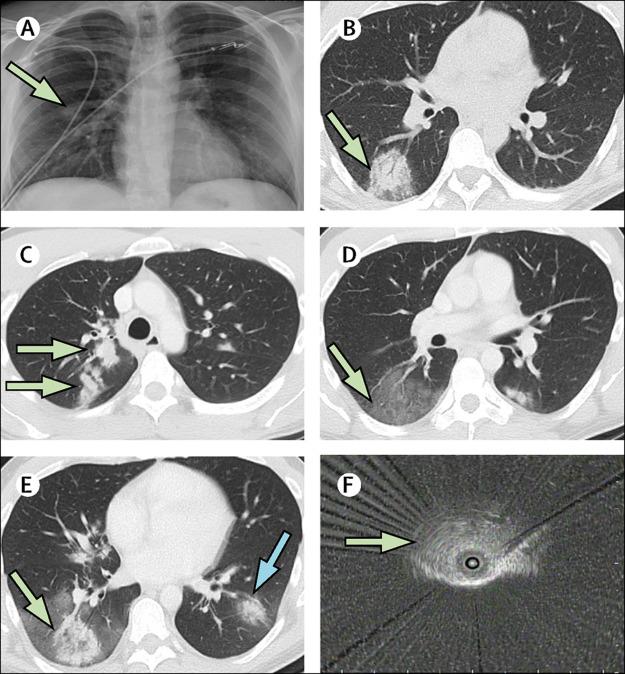

Delayed diagnosis of COVID-19 in a 34-year-old man with atypical presentation.

Delayed Diagnosis of an Atypical Pneumonia Resembling a Solitary Pulmonary Nodule.

Challenges in the interpretation and application of typical imaging features of COVID-19.